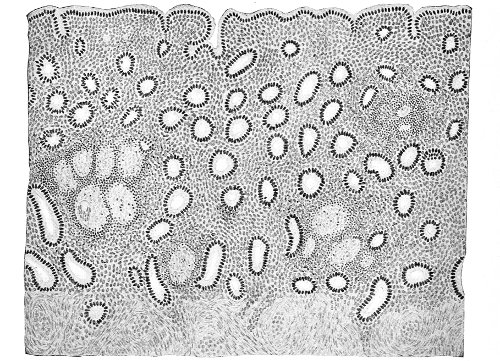

Several varieties of acute vaginitis may be recognized—the simple, the granular, the senile, and the emphysematous. It is unusual to find the entire surface of the vagina involved. The disease is confined to areas or patches separated by healthy tissue.

In simple vaginitis the inflamed membrane remains smooth.

In granular vaginitis, which is the variety usually seen, the papillæ are infiltrated with small cells, and are much enlarged, so that the inflamed surface has a granular appearance.

Senile vaginitis is due to infection of portions of the vaginal mucous membrane that have lost their epithelium as a result of the atrophic changes of old age. This disease occurs in patches of various size, sometimes presenting the character of ecchymosis; in other cases the 50 patches have altogether lost the epithelium, and permanent adhesions may take place between areas which are brought in contact. This form of vaginitis has also been called adhesive vaginitis. It is said that a similar condition may occur in children.

Acute vaginitis is accompanied by dull pain and a sense of fulness in the pelvis. The discomfort is increased by standing, walking, defecation, and urination. There is a free discharge of serum or pus, which may be tinged with blood. The character of the discharge depends upon the variety and the period of the disease. Inspection, which can best be made through the Sims speculum, with the woman in the Sims or knee-chest position, shows the characteristic lesions of inflammation of the mucous membrane.

Acute vaginitis, if neglected, may pass into the chronic form. It usually lingers in the upper part of the vagina, in the fornices, especially in vaginitis of gonorrheal origin. By careful inspection we find here one or more granular patches of inflammation, which cause a vaginal discharge from which man may be infected, and from which infection of the upper portion of the genital tract, the uterus, and the Fallopian tubes may be derived.